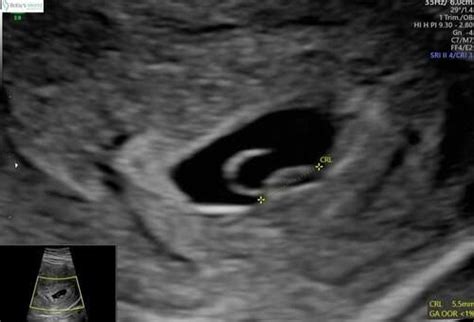

De termijnecho vindt plaats rond de 11e week van de zwangerschap. Het hoofddoel hiervan is het vaststellen van de uitgerekende datum. Dit gebeurt door de baby te meten van het hoofdje tot het stuitje (CRL - crown-rump length). Omdat baby's tot 12 weken vergelijkbare ontwikkelingsstadia doormaken en in een gelijk tempo groeien, maakt deze meting een nauwkeurige inschatting van de zwangerschapsduur mogelijk. Een baby is rond 11 weken ongeveer 40 mm groot.

Bij 6 weken zwangerschap is het embryo ongeveer 4-5 mm groot. Het wordt dan vaak omschreven als een wit vlekje met een knipperend hartje. De vruchtzak is meestal zichtbaar als een ring.